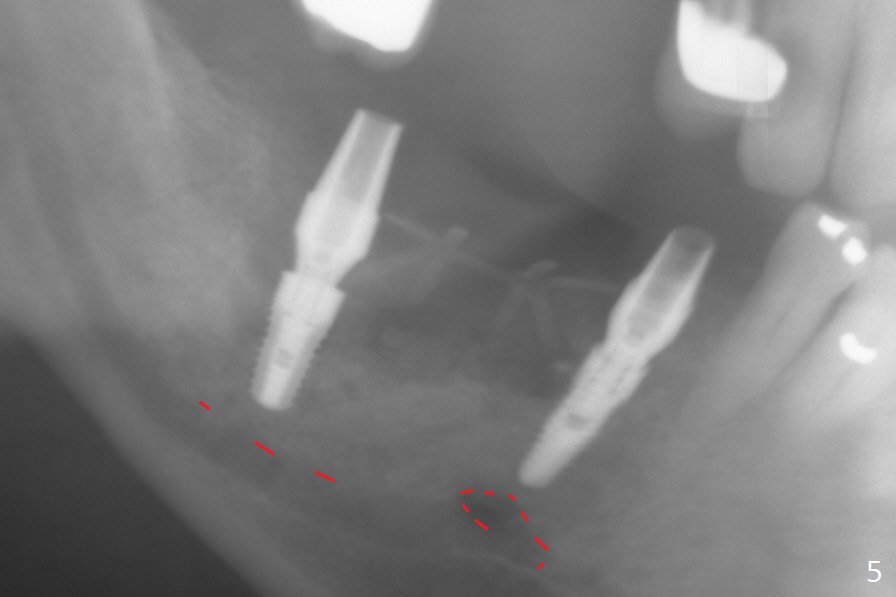

Initial osteotomy at #29-30 shows that there is clearance at #31, but not at #30 (Fig.1 (red dashed line: the superior border of the Inferior Alveolar Canal)) and that the osteotomy at #29 is close to the root of #28 (Fig.2). Moving the osteotomy of #29 distally using Lindamann bur is not sufficient (Fig.4 when a 3.8x10 mm drill is in place). A de novo osteotomy is established distally (Fig.5,6 (red dashed line: old osteotomy)).